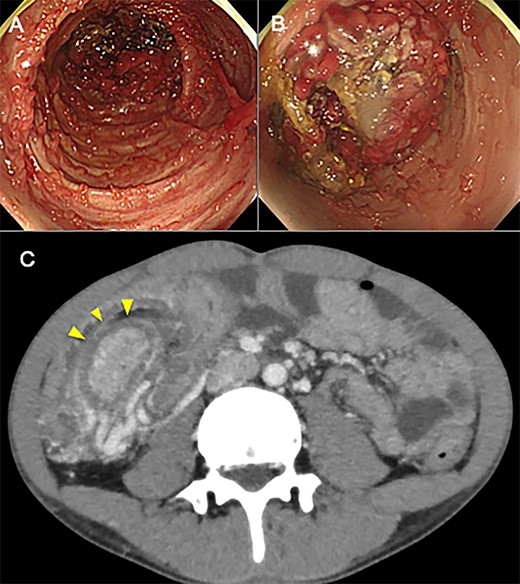

An 18-year-old man came to our hospital having initially sought treatment at the age of 16 for bloody stool. Colonoscopy revealed multiple inflammatory polyps less than 1 cm throughout the colon and the patient was diagnosed with UC by biopsy. He was initially treated with tacrolims to induce remission and was subsequently administered 5-aminosalycilic acid orally for maintenance of remission. A year later, surveillance colonoscopy failed completely because polyps in the transverse colon closed the lumen. Having no abdominal pain or the other symptoms, and no abnormalities in laboratory values, he did not undergo detailed examination at that time. Thereafter, surveillance colonoscopy the following year also failed to show the total colon, (Fig. 1A and B) a computed tomography (CT) was performed. The CT revealed elongated mass lesion in the area of the transverse colon, and the patient was diagnosed with colonic intussusception (Fig. 1C). Because he still had no symptoms, nor laboratory abnormalities, we performed to endoscopic enema reduction. Enema reduction had failed because air had passed through the lead-point of intussusception in transverse colon. Accordingly, the patient underwent elective laparoscopic total colectomy for treatment of the intussusception with UC. The operative finding revealed inversion of the transverse colon into the distal transverse colon. Histology showed widespread inflammatory polyps with no evidence of neoplasia (Fig. 2A and B). The patient’s postoperative course was uneventful, and he was discharged 28 days after surgery.

(A, B) Colonoscopy before total colectomy shows multiple polypoid structure throughout the colon, especially in the transverse colon in which colon was in invagination. (C) CT before total colectomy shows an elongated mass lesion in the transverse colon. An oval mass (arrowhead) represents intussuscepted bowel wall, surrounded by mesenteric fat and vessels of the intussuscipiens.